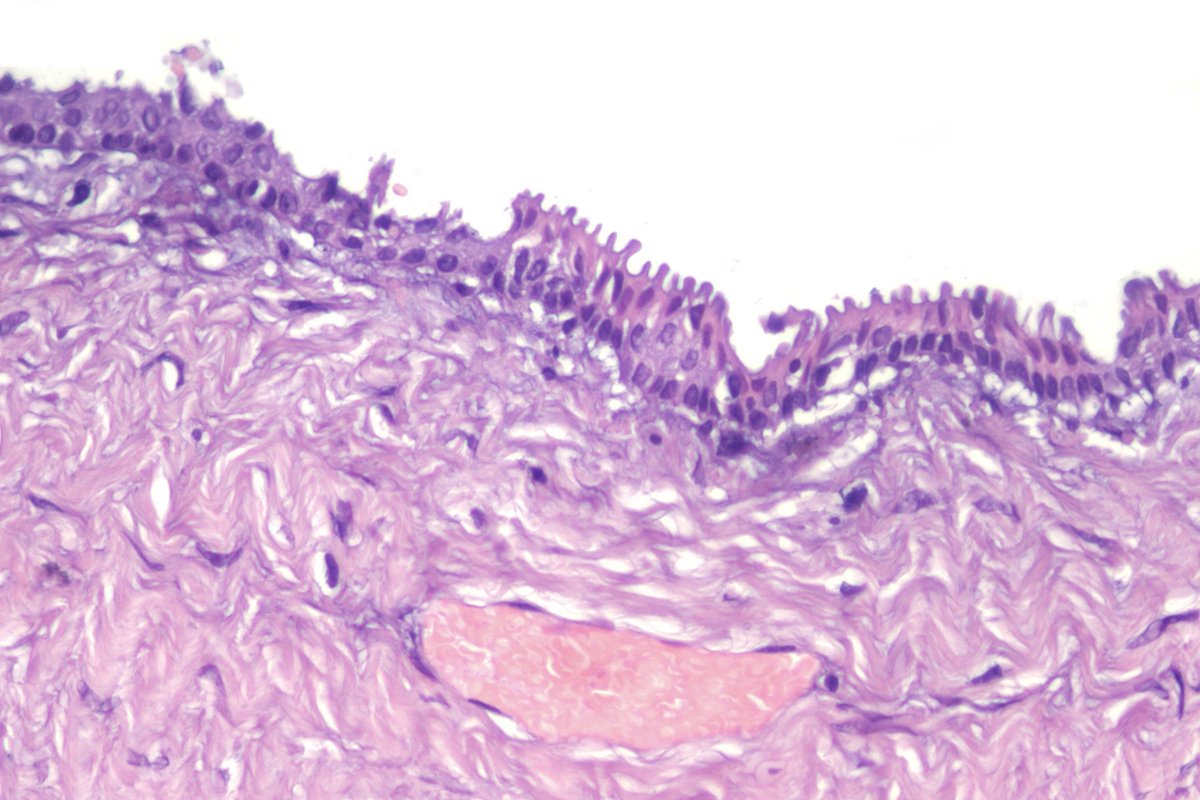

F40y,chronic cavitary pulmonary aspergillosis, atypical resection of the low lobe of the lung.

several cavities with a fungal ball, granulation tissue, chronic inflamation, metaplastic squamous epithelium, calcium oxalate crystals